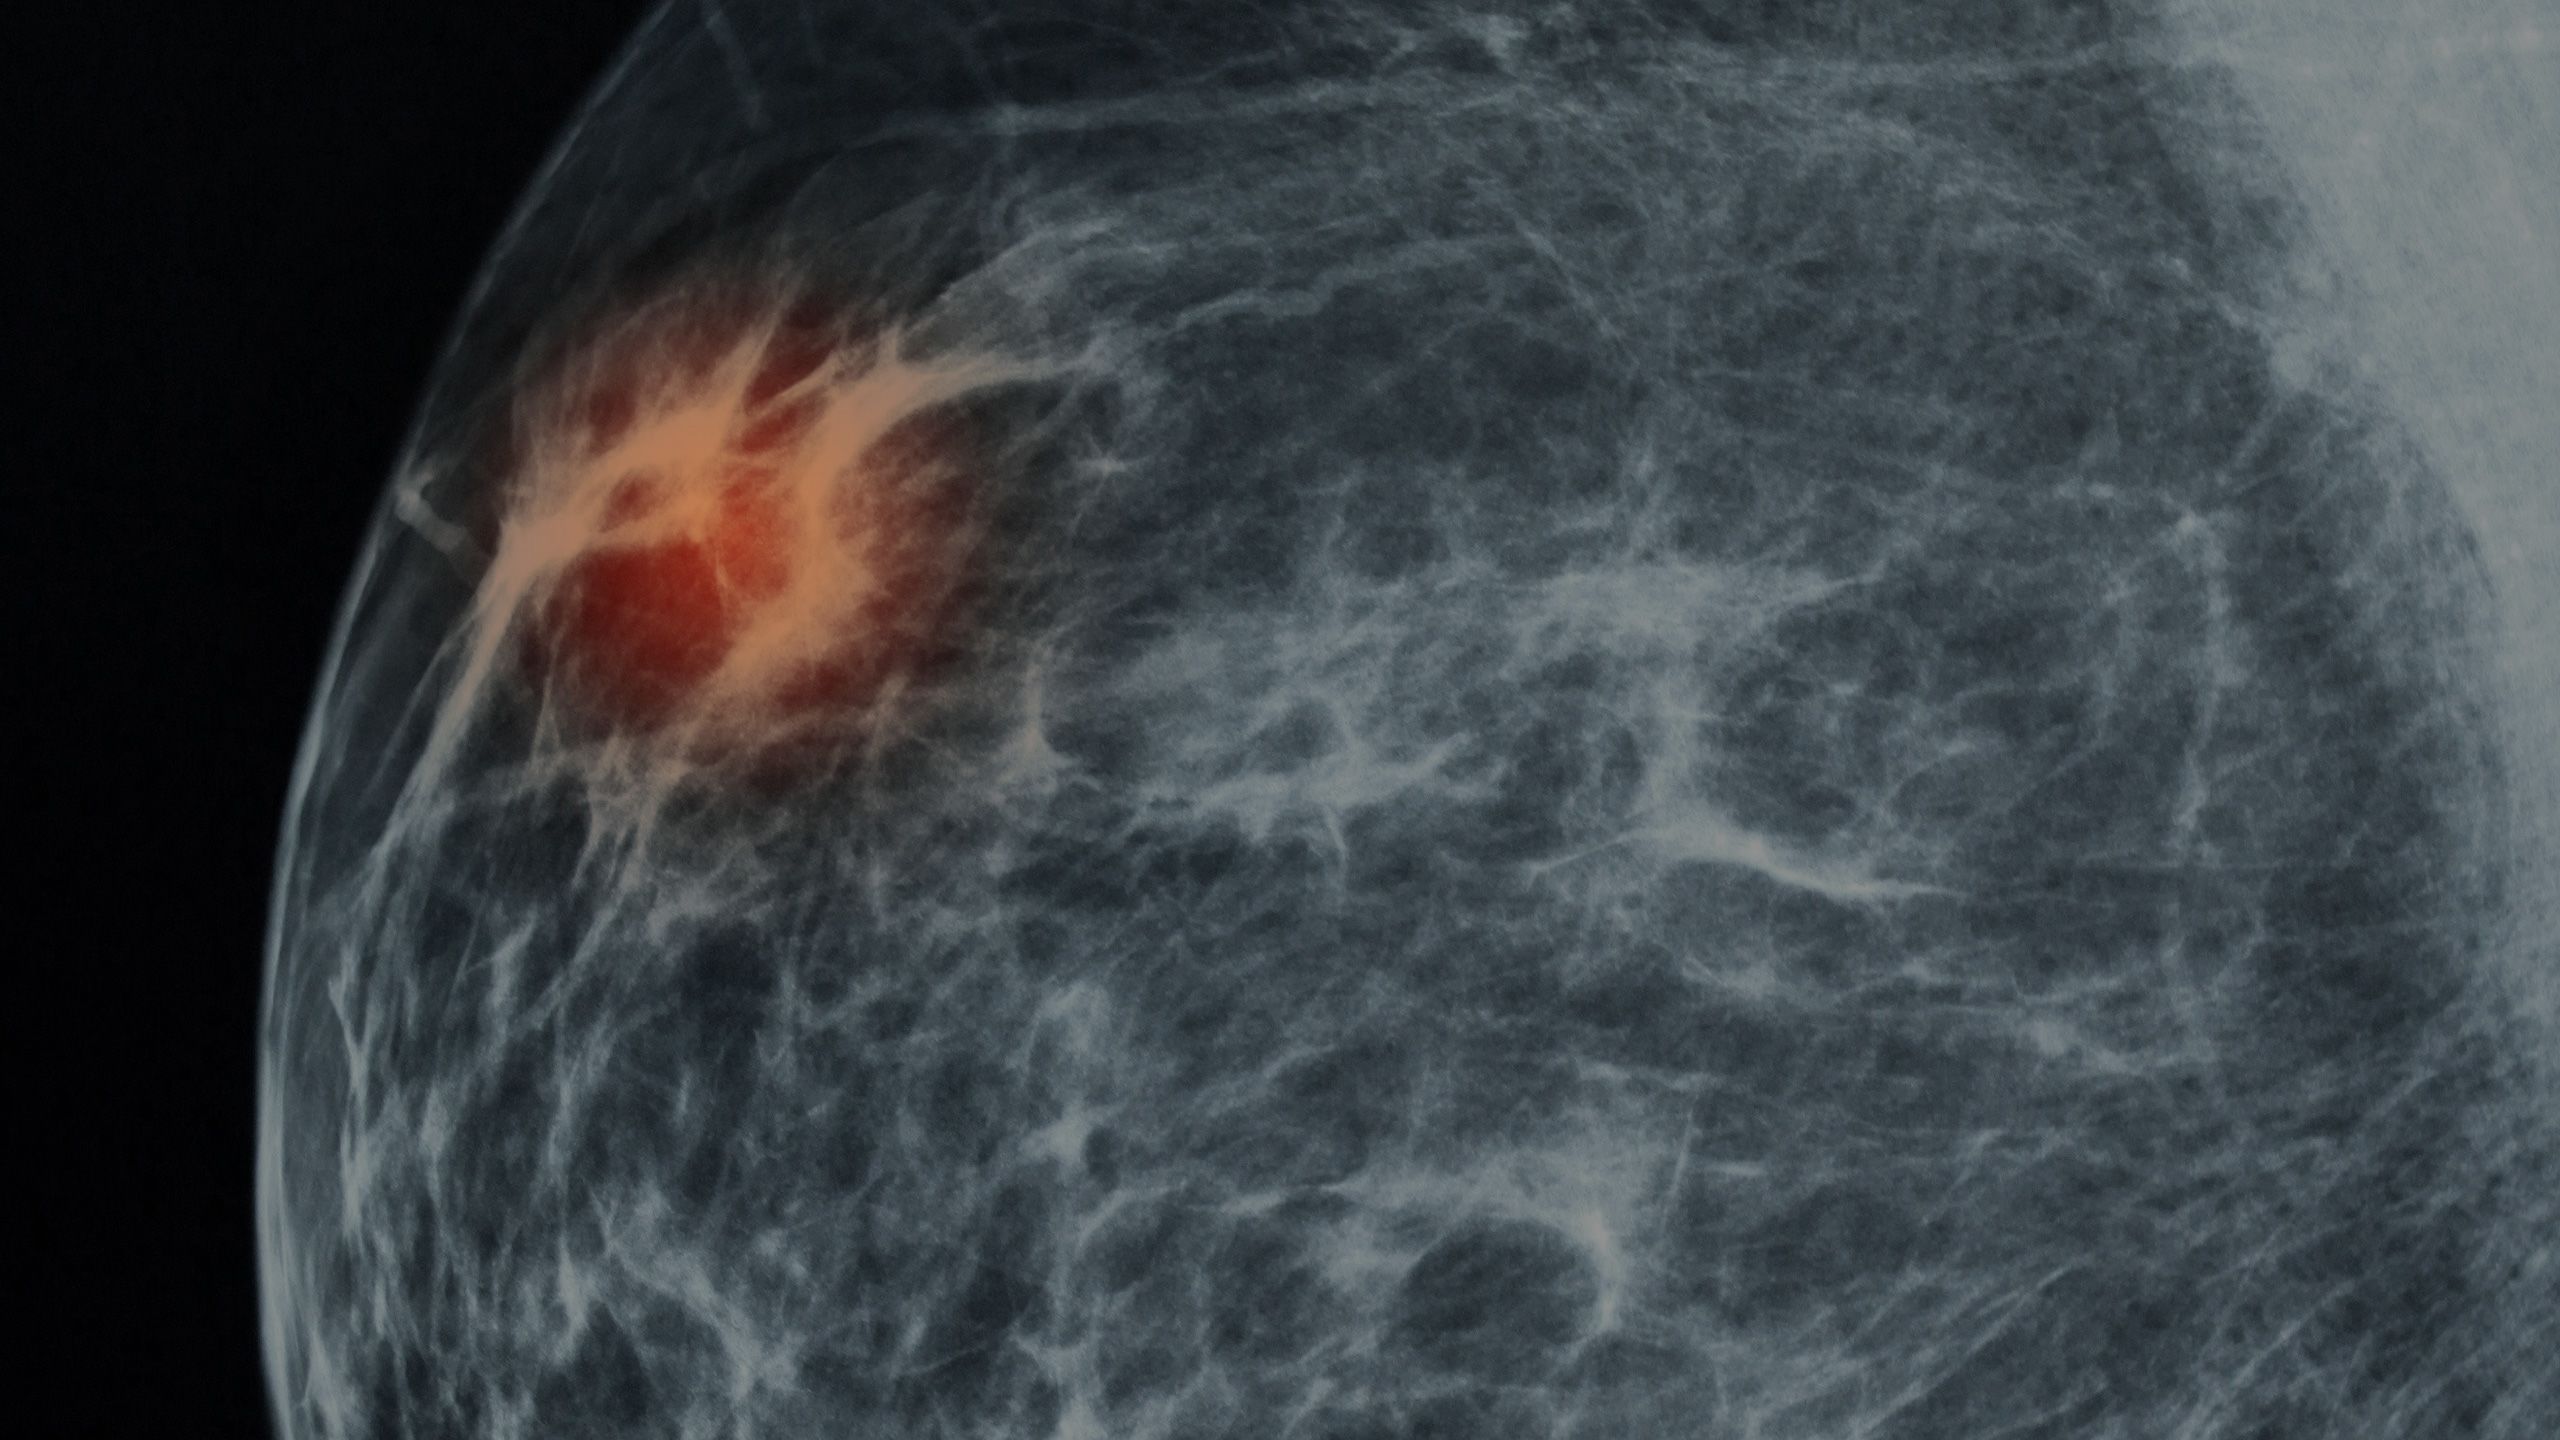

The sonographer called a radiologist for advice on the spot, telling King she would likely need a mammogram. In New Zealand, free breast screening (a mammogram every two years) starts at 45. At just 37, King had never needed one.

Scans revealed three tumours. The largest two measured 4.5cm. The size of plums.

The cancer was HER2-positive. Aggressive, fast growing and more likely to recur after chemotherapy than other breast cancers. The prognosis for women with this kind of breast cancer is worse than those whose cancer was not HER-2 positive.

More than 400 women are diagnosed with HER2-positive breast cancer each year in New Zealand, accounting for approximately 20 per cent of breast cancers. Formally known as human epidermal growth factor receptor 2 (HER2) the cells have higher than normal levels of protein, causing the cancer to grow and spread rapidly.